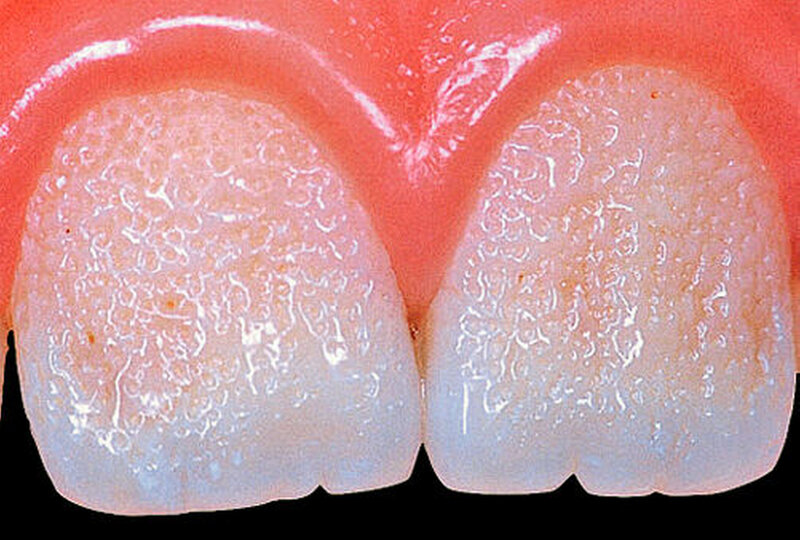

Bei dieser genetisch bedingten Schmelzdysplasie sind in der Regel alle Zähne einer oder beider Dentitionen betroffen, und es ist ein bilateralsymmetrisches Erscheinungsbild vorhanden. Die Ausprägung der Schmelzdefekte kann von Zahn zu Zahn und von Generation zu Generation variieren (Abbildungen 1a bis 1c). Die Struktur des Dentins ist nicht verändert. Die Schmelzdefekte treten als Grübchen von unterschiedlicher Größe in mehr oder weniger normal dickem Schmelz in Erscheinung (Abbildung 2a). Durch Einlagerung von Farbstoffen in diese Grübchen können die Schmelzveränderungen ästhetisch störend wirken (Abbildung 2b). Ähnliche grübchenartige Schmelzhypoplasien können bei Patienten mit Rachitis, Pseudohypoparathyroidismus oder Epidermolysis bullosa beobachtet werden. Bei der hypoplastischen Form der Amelogenesis imperfecta ist die Schmelzhärte normal, die Schmelzdicke jedoch reduziert. Der grübchenartige Typ weist als Ausnahme eine fast normale Schmelzdicke auf (Abbildungen 3 und 4).